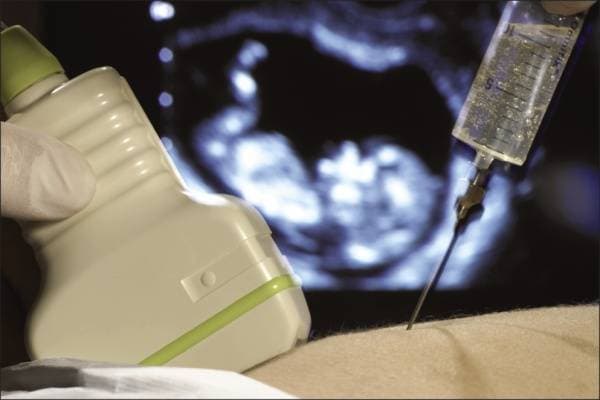

Chọc ối xét nghiệm có đau không là quan tâm của nhiều thai phụ.

Quá trình chọc ối xét nghiệm chỉ diễn ra trong khoảng 30 phút. Bác sĩ sẽ siêu âm xác định vị trí chọc ối ở một khoảng cách an toàn cho thai nhi, sau đó, dưới sự hỗ trợ của việc siêu âm, bác sĩ sẽ dùng một mũi kim mỏng, dài và rỗng đưa xuyên qua màng bụng và tử cung của mẹ để trích ra một lượng nhỏ nước ối. Thai phụ có thể cảm thấy đau rút, nhói, hoặc áp lực trong quá trình chọc ối với mức độ khó chịu khác nhau tùy từng thai phụ và giai đoạn thai kỳ.

Thai phụ nên lựa chọn các cơ sở y tế uy tín để thực hiện chọc ối xét nghiệm.